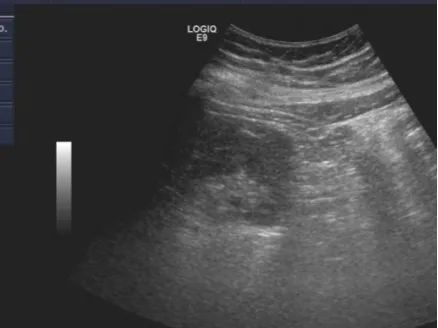

超声引导下肾穿刺后肾周血肿

腹腔镜下肾穿刺后肾周无明显血肿